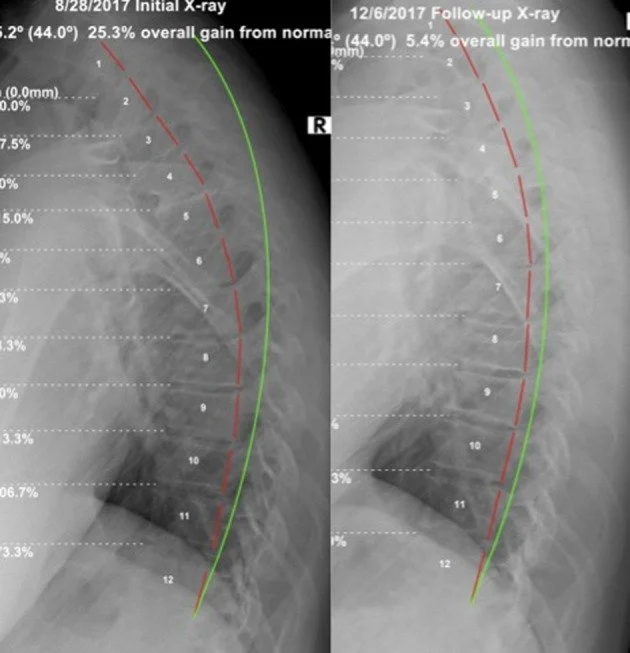

Fig. 2. Lateral thoracic radiographs. Left: Initial (8/28/17); Right: Follow-up (12/6/17). Green line indicates normal thoracic kyphosis; red line highlights patient posterior vertebral body margins (CBP Seminars, Inc.).